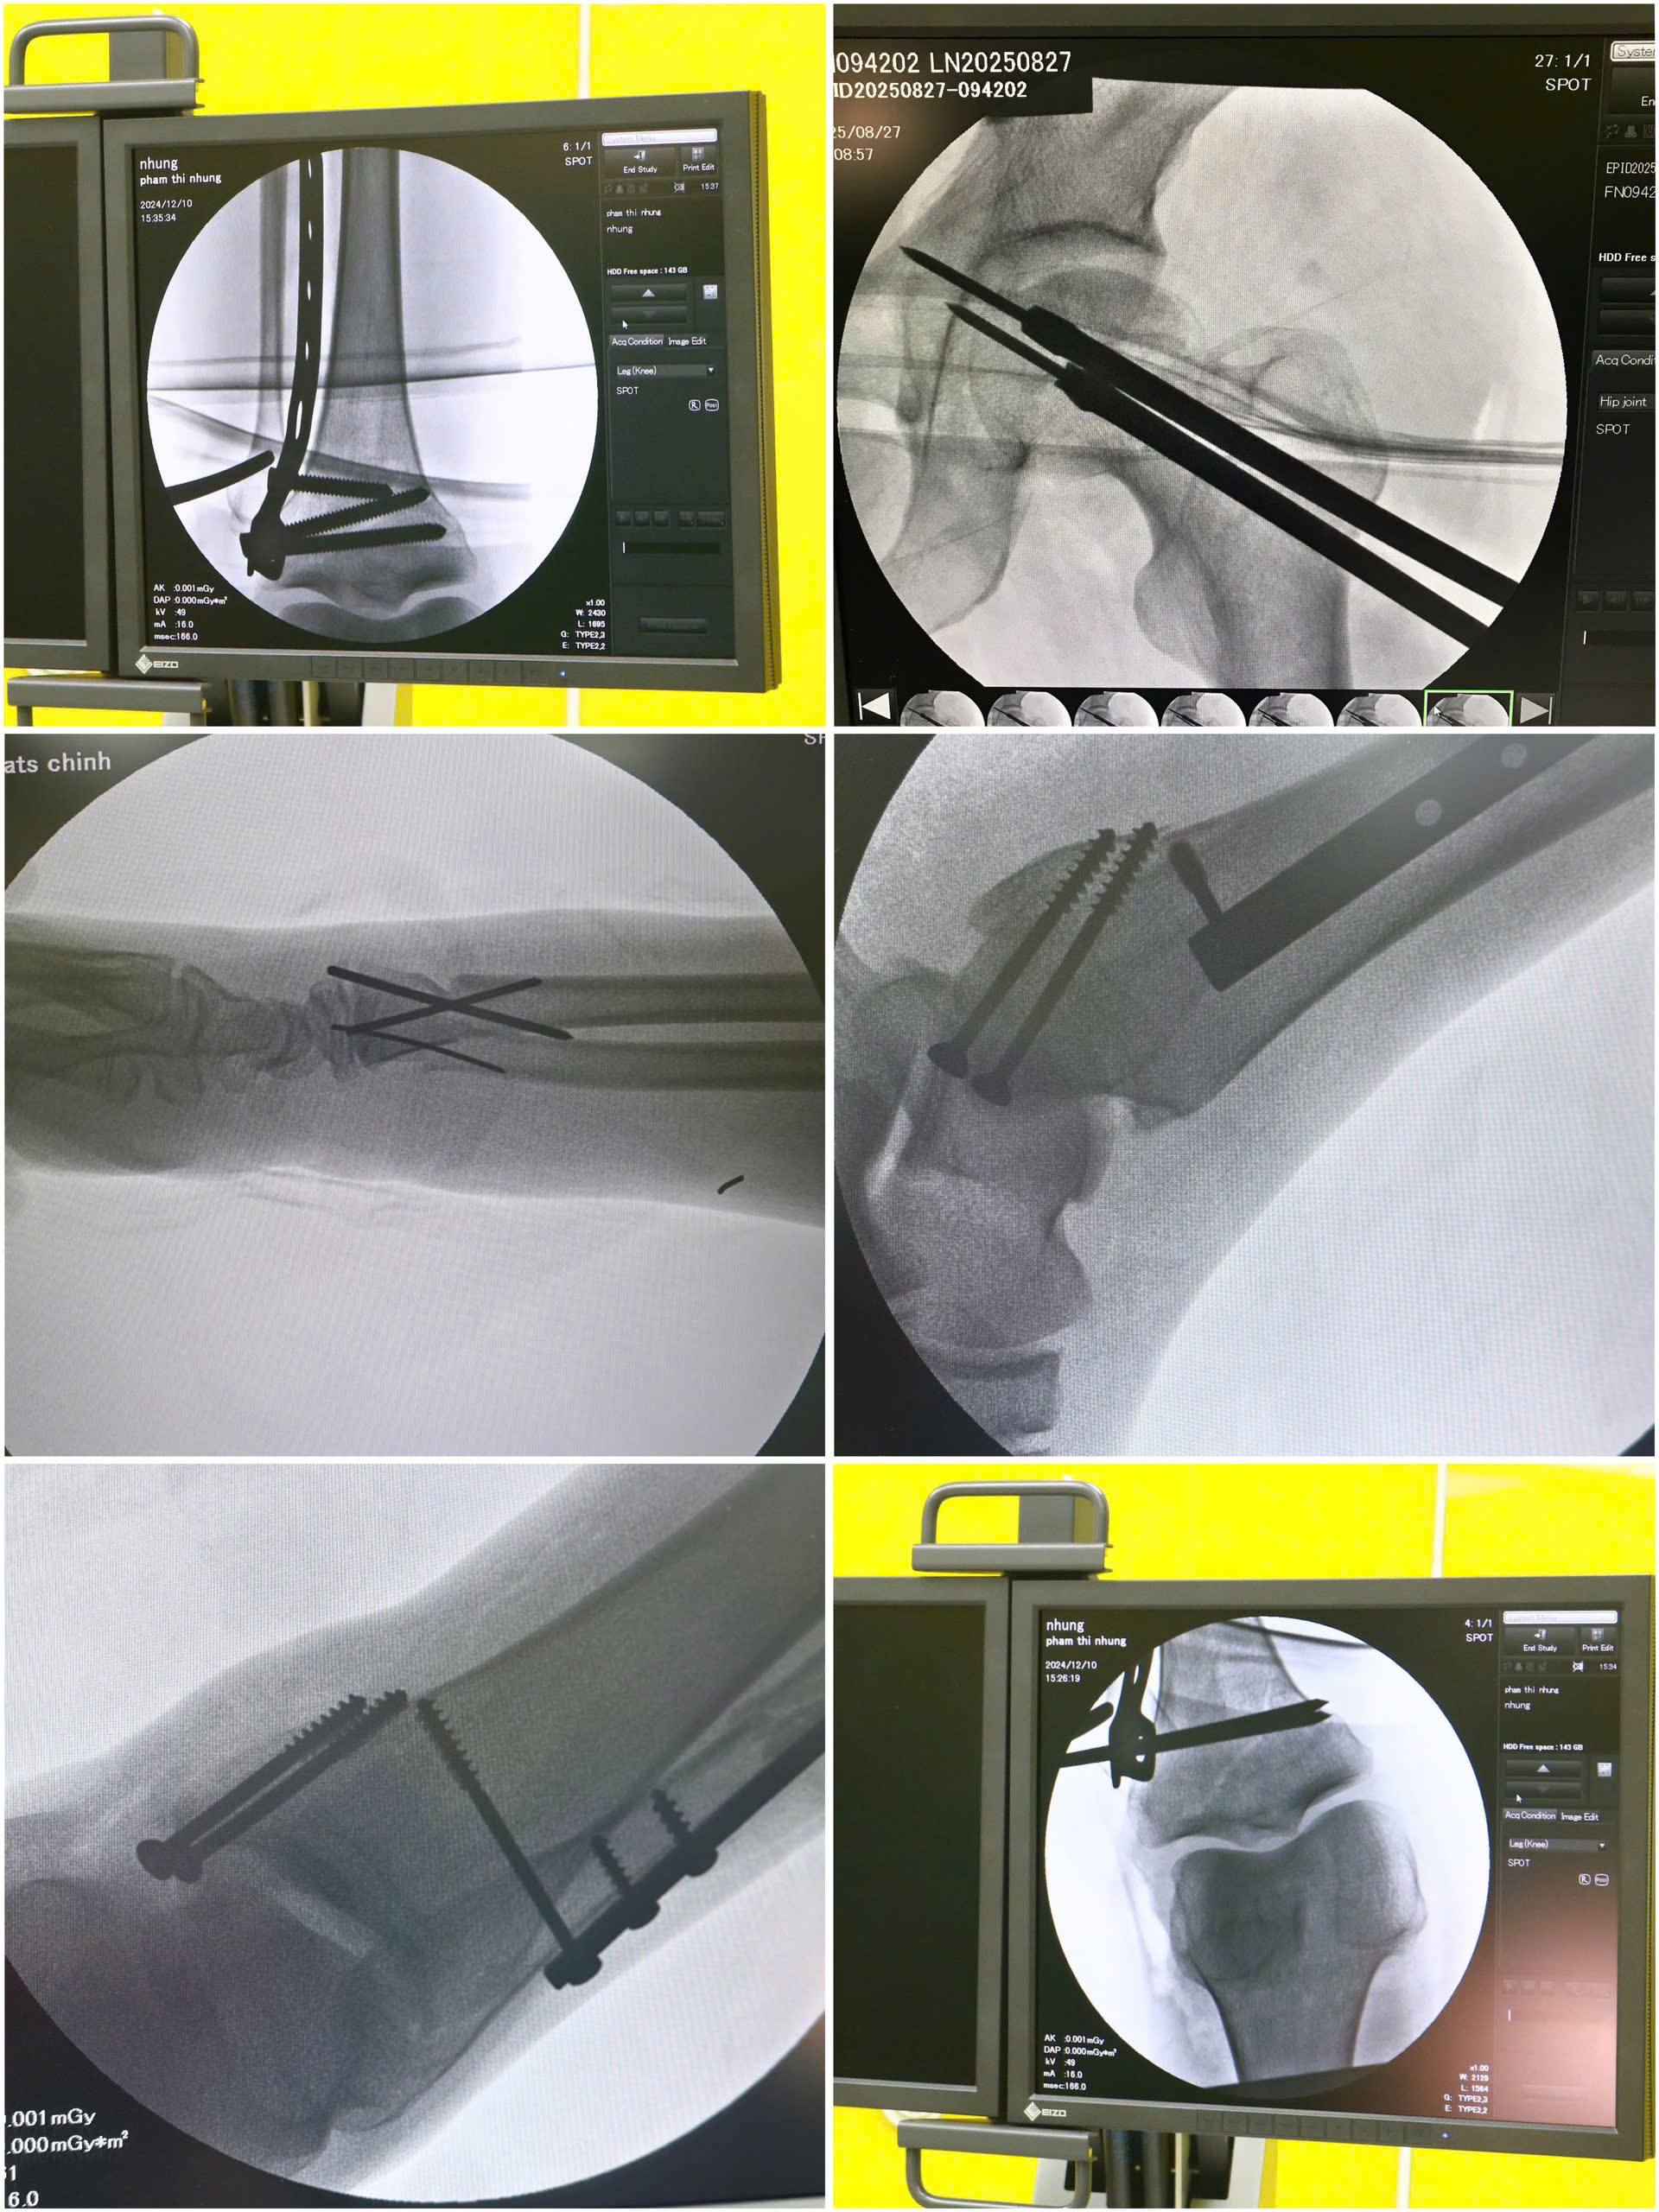

Chuyên môn vững vàng kết hợp hệ thống máy C-arm hiện đại trong điều trị chấn thương chỉnh hình tại Trung tâm Y tế Thị xã Quảng Yên

Trong vòng một tuần trở lại đây, TTYT Thị xã Quảng Yên liên tục tiếp nhận nhiều ca tai nạn giao thông và tai nạn sinh hoạt gây gãy xương chi trên, chi dưới, trật khớp, chấn thương phức tạp. Trước đây, nhiều trường hợp phải chuyển tuyến, nhưng nay với đội ngũ bác sĩ có chuyên môn vững vàng cùng hệ thống máy C-arm hiện đại, các ca phẫu thuật chấn thương đã được xử trí hiệu quả ngay tại địa phương.

Máy C-arm là thiết bị X-quang tăng sáng truyền hình hiện đại, được xem như “con mắt thứ hai” của phẫu thuật viên trong phòng mổ. Với khả năng cung cấp hình ảnh trực tiếp, rõ nét và tức thì, máy C-arm mang lại nhiều lợi ích thiết thực trong phẫu thuật chấn thương chỉnh hình:

• Định vị chính xác vị trí tổn thương xương: hỗ trợ bác sĩ nhanh chóng xác định đường gãy, vị trí cần can thiệp và hướng dẫn đặt đinh, nẹp, vít một cách chuẩn xác, hạn chế tối đa sai lệch.

• Kỹ thuật ít xâm lấn: giúp giảm sang chấn mô mềm, hạn chế mất máu, bảo tồn tối đa cấu trúc xung quanh.

• Rút ngắn thời gian mổ: nhờ kiểm soát trực tiếp trên hình ảnh, phẫu thuật được tiến hành thuận lợi, giảm thiểu nguy cơ tai biến trong mổ.

• Theo dõi tức thì kết quả: ngay sau khi cố định xương, bác sĩ có thể kiểm tra ngay hiệu quả phẫu thuật, bảo đảm chắc chắn và an toàn, đồng thời giảm thiểu nguy cơ phải can thiệp lại.

Tại TTYT Thị xã Quảng Yên, sự kết hợp giữa chuyên môn vững vàng của đội ngũ bác sĩ ngoại chấn thương chỉnh hình và hệ thống thiết bị hiện đại như máy C-arm đã tạo ra những kết quả điều trị vượt trội:

Trong tuần qua, nhiều bệnh nhân gãy xương chi trên, chi dưới do tai nạn đã được phẫu thuật thành công bằng sự hỗ trợ của máy C-arm. Sau mổ, hầu hết người bệnh đều tỉnh táo, ít đau, có thể vận động sớm và tinh thần thoải mái.